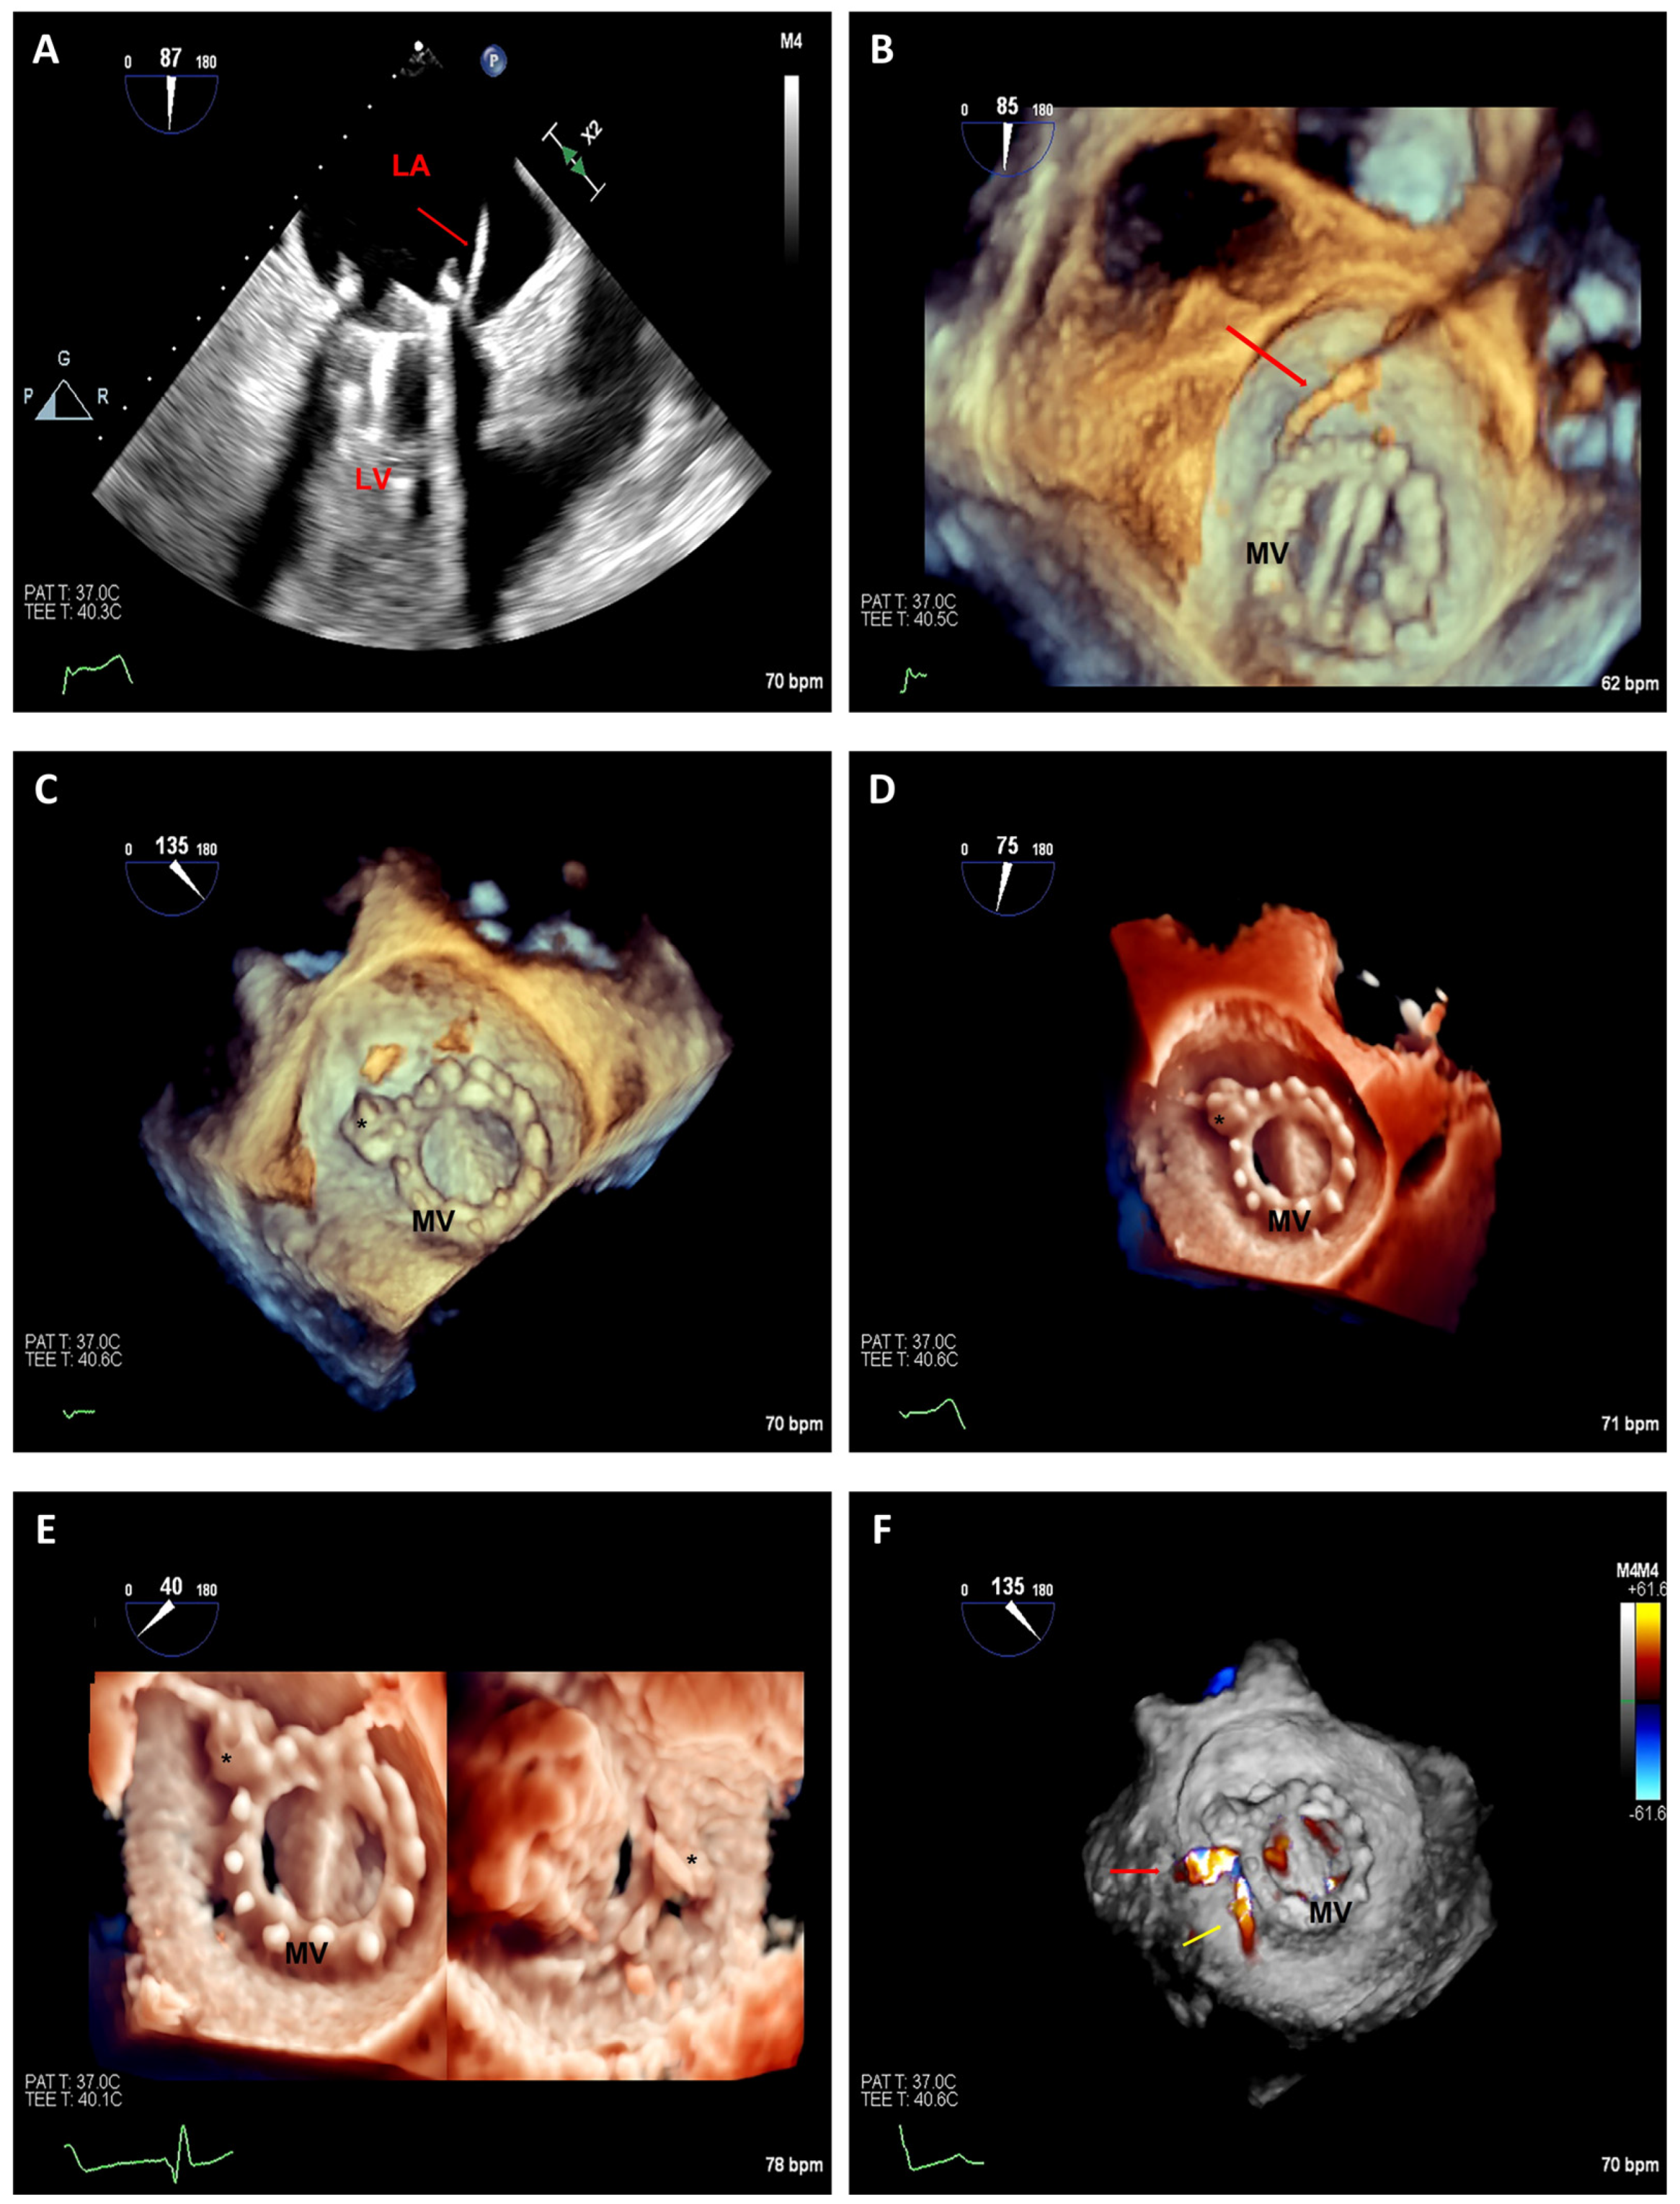

3.2.2. Transcatheter Mitral Valve Replacement

3.3. Paravalvular Leak Closure